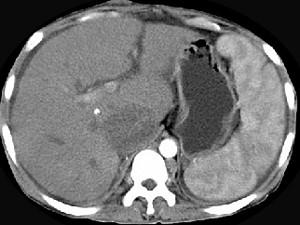

问题 女性,26岁,腹胀不适7月,腹软,肝右肋缘下1cm,影像检查如图,可能的诊断为 ( )

选项 A、布加综合征 B、脂肪肝 C、原发性肝癌 D、肝硬化腹水 E、肝血管瘤

答案 A